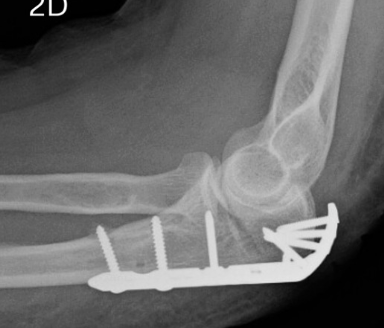

Distal Humerus Fractures

Complex bicolumnar fractures of the distal humerus — classification by AO/OTA system (A = extra-articular, B = partial articular, C = complete articular). They are challenging injuries requiring precise restoration of the articular surface and both columns to restore elbow function:

- ORIF with dual pre-contoured locking plates: Standard technique for Types B and C fractures. Orthopaedic surgery of significant complexity, typically requiring 2–3 hour operative time.